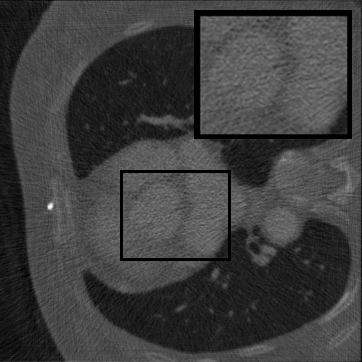

Figure 3: Qualitative completion results on TomoBank (lines 1 to 2) and LoDoPaB (lines 3 to 4) with random mask (ratio = 0.8) at 1024×\times1024 resolution. Odd columns and even columns show the sinograms and reconstructed images, respectively.

Tab 2 summarizes accuracy results. At 2048×\times2048 resolution, HRSino achieves the best performance among all baselines while remaining memory-efficient, demonstrating its ability to extend high-quality completion to resolutions where other diffusion models fail. At 1024×\times1024, HRSino delivers accuracy comparable to its computation-intensive counterpart RePaint, showing that our optimizations do not compromise fidelity at moderate scales. Compared to DiffIR, MCG, TD-Paint, and HiDiffusion, HRSino consistently achieves higher SSIM and PSNR across mask ratios, with improvements up to +0.03 SSIM and +1.8 dB PSNR. Fig 3 visualizes sinogram completion and reconstructed images, where HRSino produces nearly indistinguishable results from RePaint. These findings confirm that HRSino fundamentally extends diffusion-based completion to 2048×\times2048 resolution in a more memory- and runtime-efficient manner.